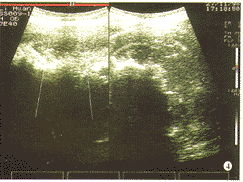

56例治疗后肿瘤边界变得模糊,体积缩小,回声增强而不均匀。较大的肿瘤在 15 d 左右可出现液化灶,常位于病变的中心,大小不等,若继续向周边扩展,可形成蜂窝状结构。在2个月后可见到钙化灶征象。HIFU治疗后肿瘤明显缩小的时间一般在 3~6 个月以后,通常在6个月左右才开始明显缩小。2例小肝癌的体积在治疗后1个月明显缩小。CDFI显示治疗后血供消失(图1,2),部分患者仍可见肿块边缘散在稀疏的点状彩色血流,以静脉血供为主。6例(10.7%)肿瘤直径在 10 cm以上,患者身体状况极差,只作了“减瘤”或部分切除治疗,治疗区回声增强,血供消失,未治疗区血供仍丰富。这6例的平均生存时间为6个月。8例在第1次治疗后1个月检查,疗效欠佳,实施第2次治疗后,回声增强,血供消失。42例至今仍健在,随访时间最长者超过18个月。

图1 肝癌患者HIFU治疗前,血供丰富

图2 与图1为同一患者,HIFU治疗11 d后,病灶缩小,血供消失